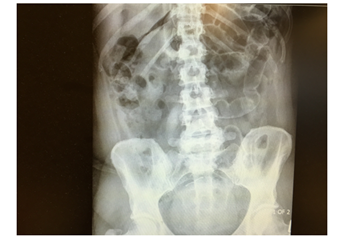

Her inflammatory markers were raised with C reactive protein (CRP) reading at 150 mg/L and White cell count of 10.2X 109. Erect chest X-ray showed large amount of air under the diaphragm and abdominal X-ray showed dilated small bowel loops (Figure 2) in the left upper quadrant and free air between the loops. The patient underwent emergency laparotomy with hissing of air escape at peritoneal opening. All organs were examined and no abnormality was seen. All four quadrants examined thoroughly but no evidence of any bowel leak found. There were no signs of any inflammation in pelvis and a negative laparotomy was concluded. The patient had uneventful recovery and was discharged home on 4th post-operative day. The patient underwent further abdominal and pelvic CT scan Figure 3-5 with contrast few days after the operation for completion of investigation and no abnormality was seen. The patient was reviewed in the clinic one and three months after the operation with no complaint and no post-operative complications.

Figure 2 Dilated Small bowel loops in Left upper quadrant.